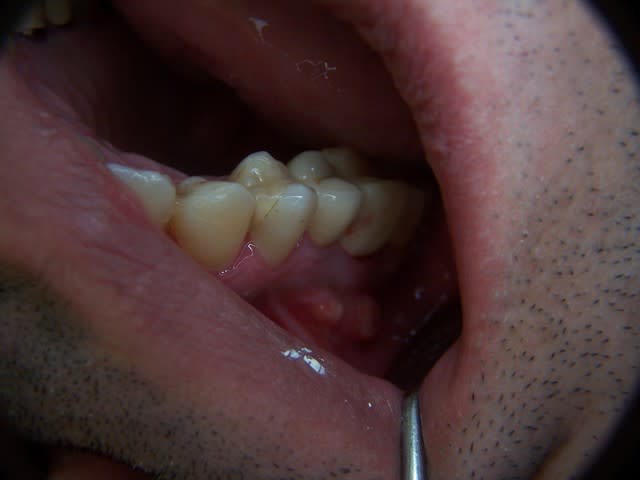

etlà, en bouche, 2 gros abcès , l'un à l'apex de 15, l'autre un peu en distal de l'apex de 16. les 2 fistules sont distantes de presque 1 cm. Le patient dit avoir toujours un peu mal.

La dent est mobilité 1 aujourd'hui.